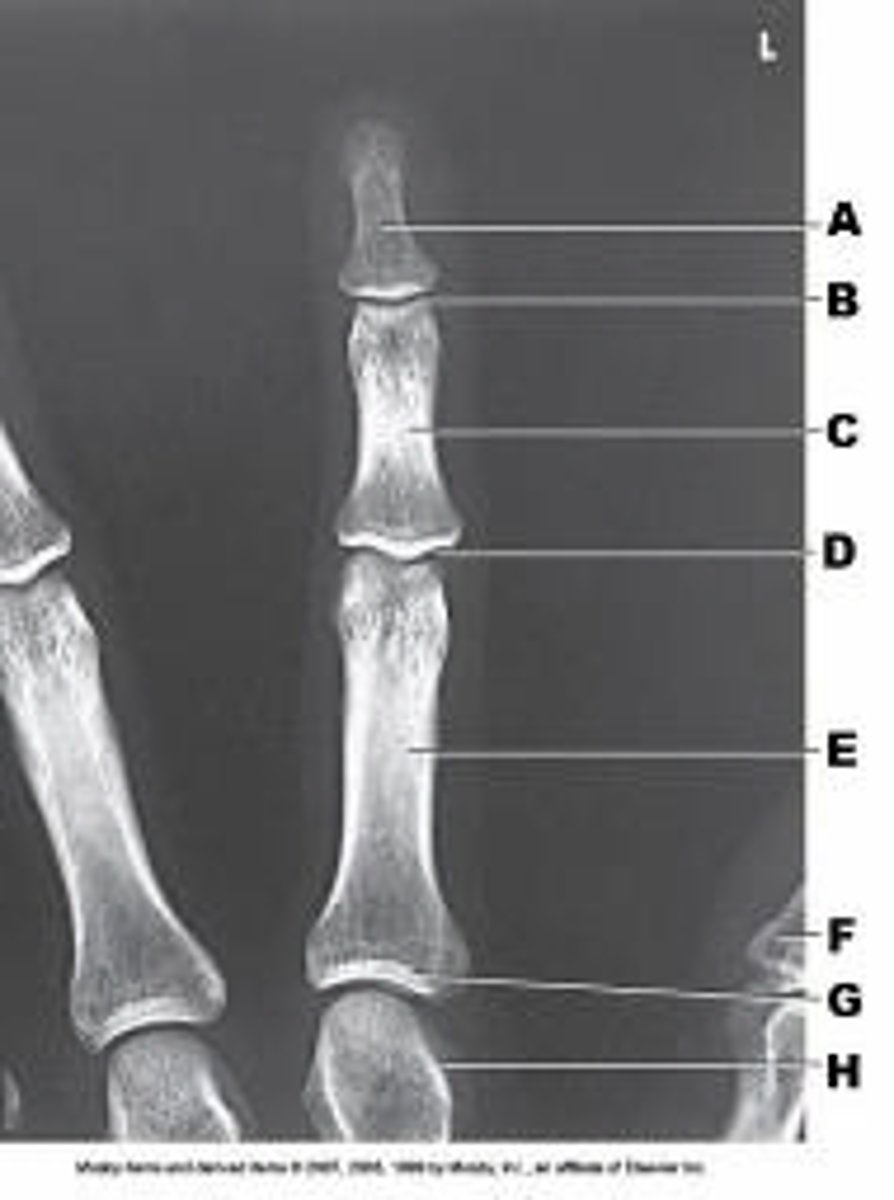

First metatarsophalangeal joint

Proximal IP joint